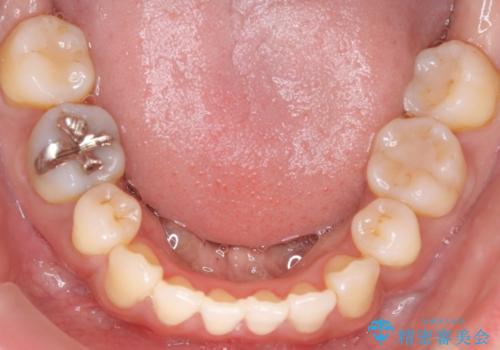

上顎の前歯は前方に傾斜しており、下あごの前歯にもガタガタがありました。

上下左右の小臼歯を合計4本抜歯して矯正することとしました。